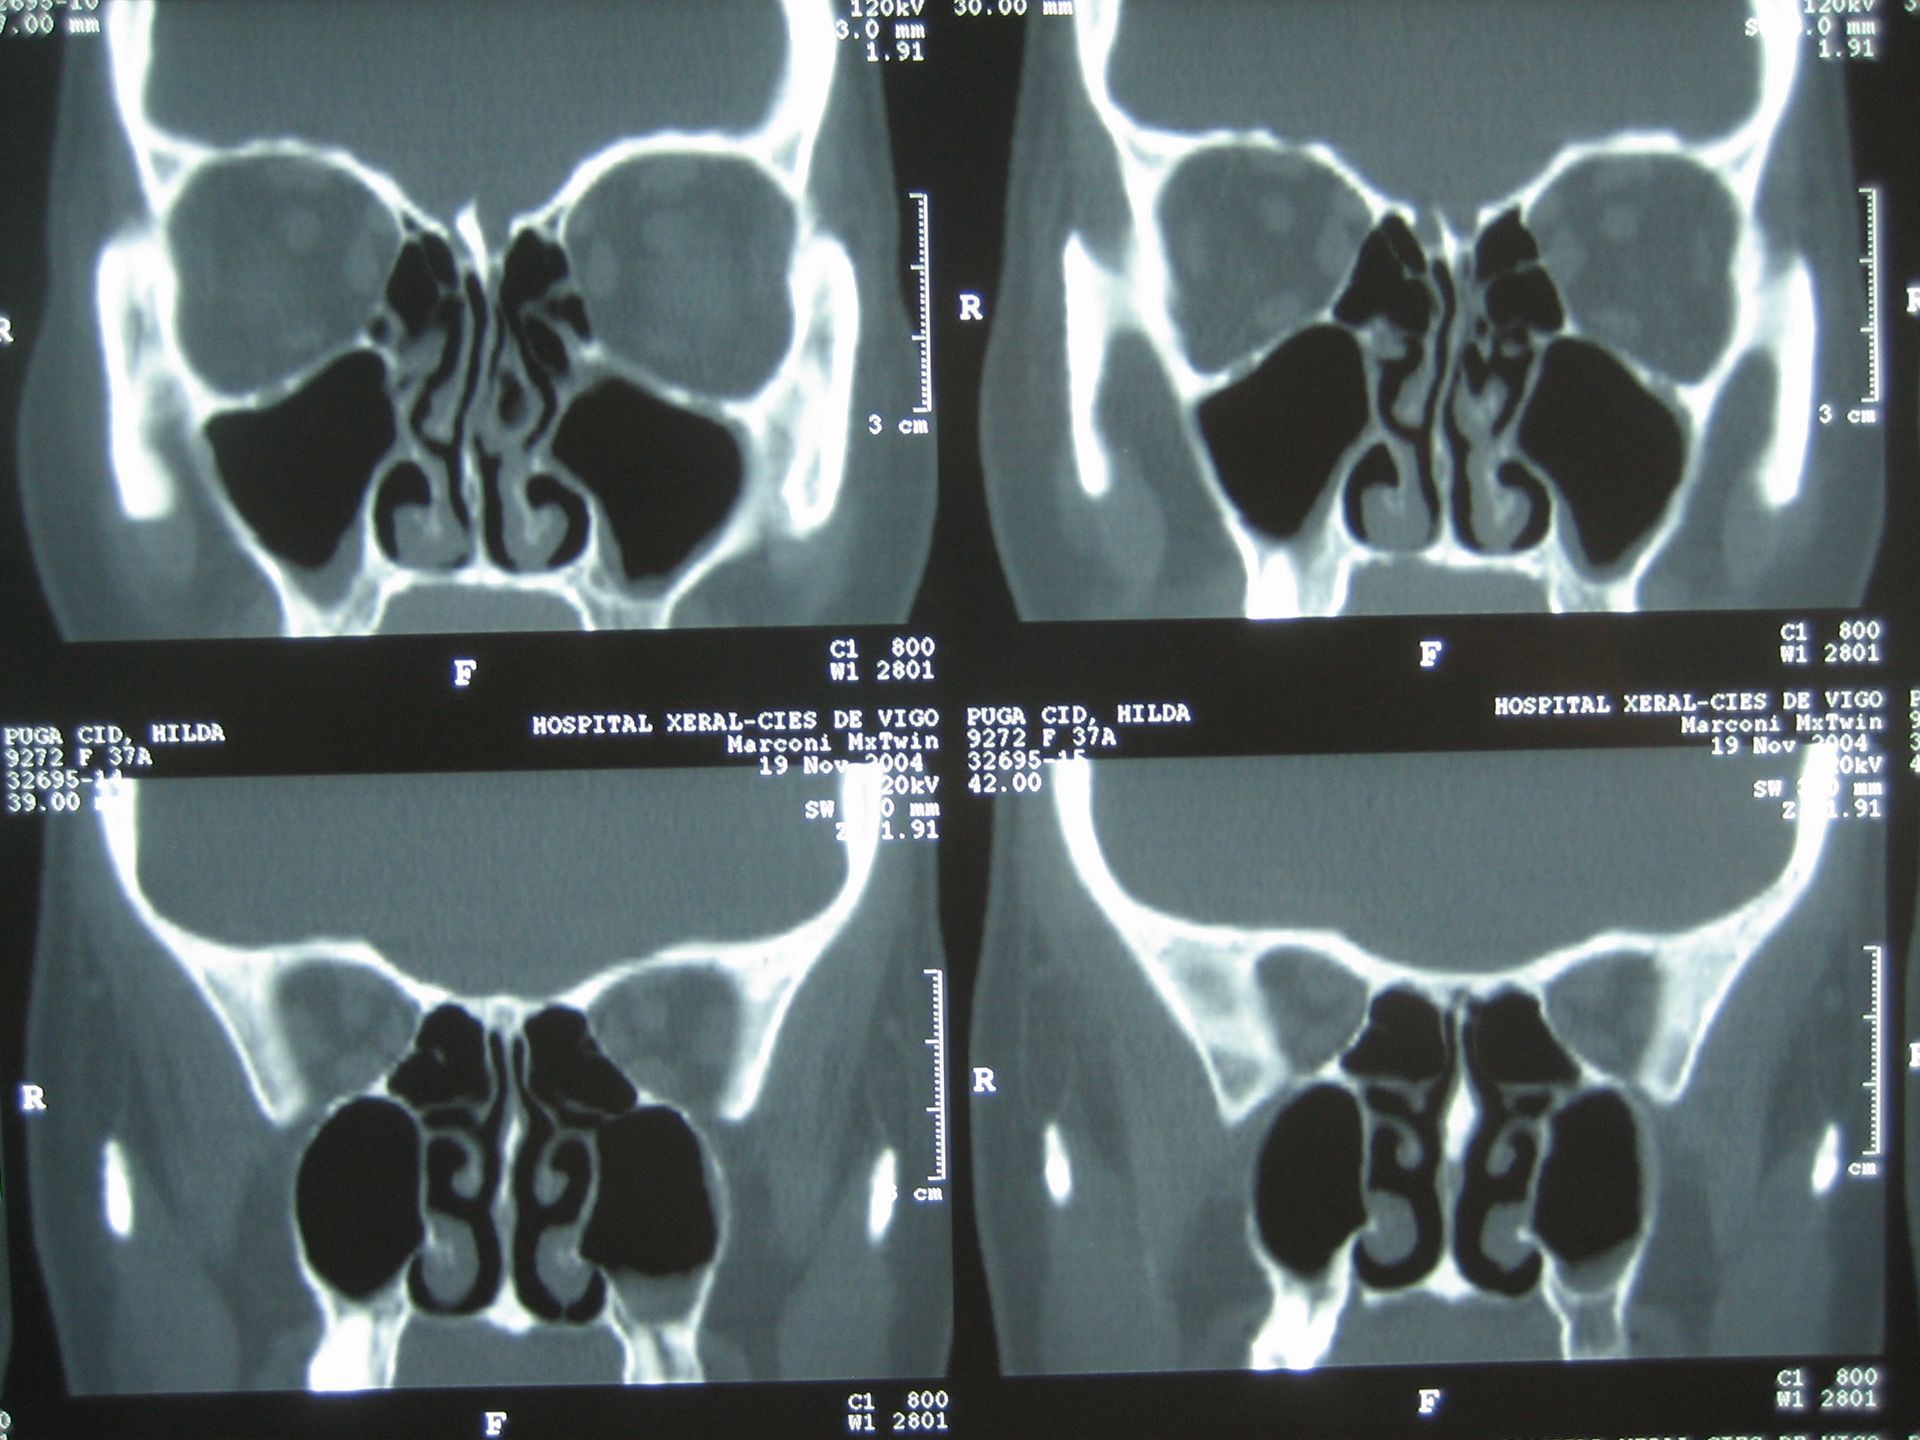

EXPERTO EN ENFERMEDADES DE NIÑOS Y DE LA NARIZ Y SENOS PARANASALES

En nuestra clínica, nos enfocamos en proporcionar soluciones efectivas para una variedad de problemas relacionados con la salud del oído, nariz y senos paranasales. Nuestro objetivo es ofrecer tratamientos avanzados y personalizados a cada paciente.